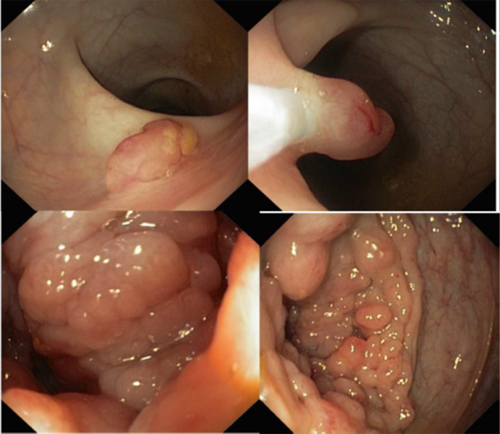

MCAS were observed in nearly one-third (7/23, 30%) of patients. These symptoms included flushing, fever, malaise, diarrhea and tachycardia. The most common organ involved was bone (78%), with masses found in the thoracic vertebrae, pelvis, tibia, femur, ankle and skull; followed by the gastro-intestinal tract (35%) (Figure 1); lymph nodes (30%); skin (30%); spleen (26%); and liver (22%) (Table 1). Sarcoma may also be localized in the uterus (n = 1), testicles (n = 1), oropharyngeal tract (including the lips, ears and larynx (n = 3)) and eyes (n = 1). Of note, all 5 pediatric cases had bone localization (Table 1), and 80% (n = 4) of these had cephalic bone localization, including the temporal bone, external auditory tract and ear. This could suggest that careful clinical long-term follow-up of children and young adults with mastocytosis is necessary and may include examinations of the head, ears and skull for the children.

Figure 1: Endoscopic findings of a gastro-intestinal mast cell sarcoma (# 23). There is a burgeoning polylobar tissue lesion of the right colon (arrow).